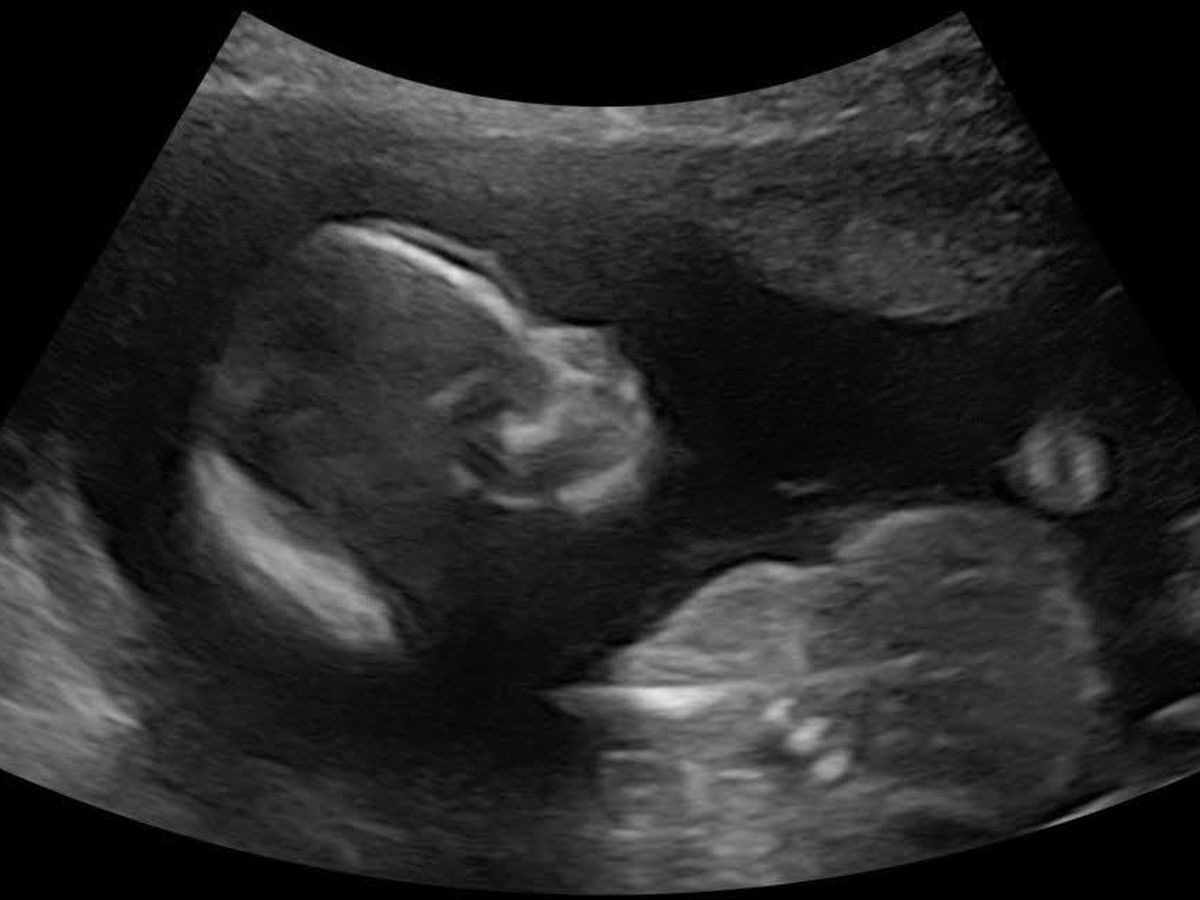

With two loving but rambunctious toddler boys at home in Stansbury Park, Utah, my sister-in-law Jani Grover Mangelson was hoping the next baby would be a girl when she found out she was pregnant. But the news of the hoped-for princess came with other news: the baby, named Mia Sue, has trisomy 18, or Edward's Syndrome.

For the last few months, Jani and her husband, Jesse Mangelson, have endured the ups and downs of the unknown while they've felt Mia grow. Jani says Mia has been a very active baby--even more active than her two older brothers, 4-year-old Jude and 2-year-old Benjamin, were!